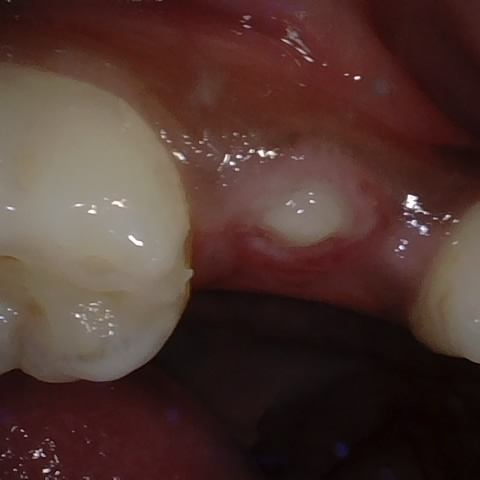

Annotated as "Good"